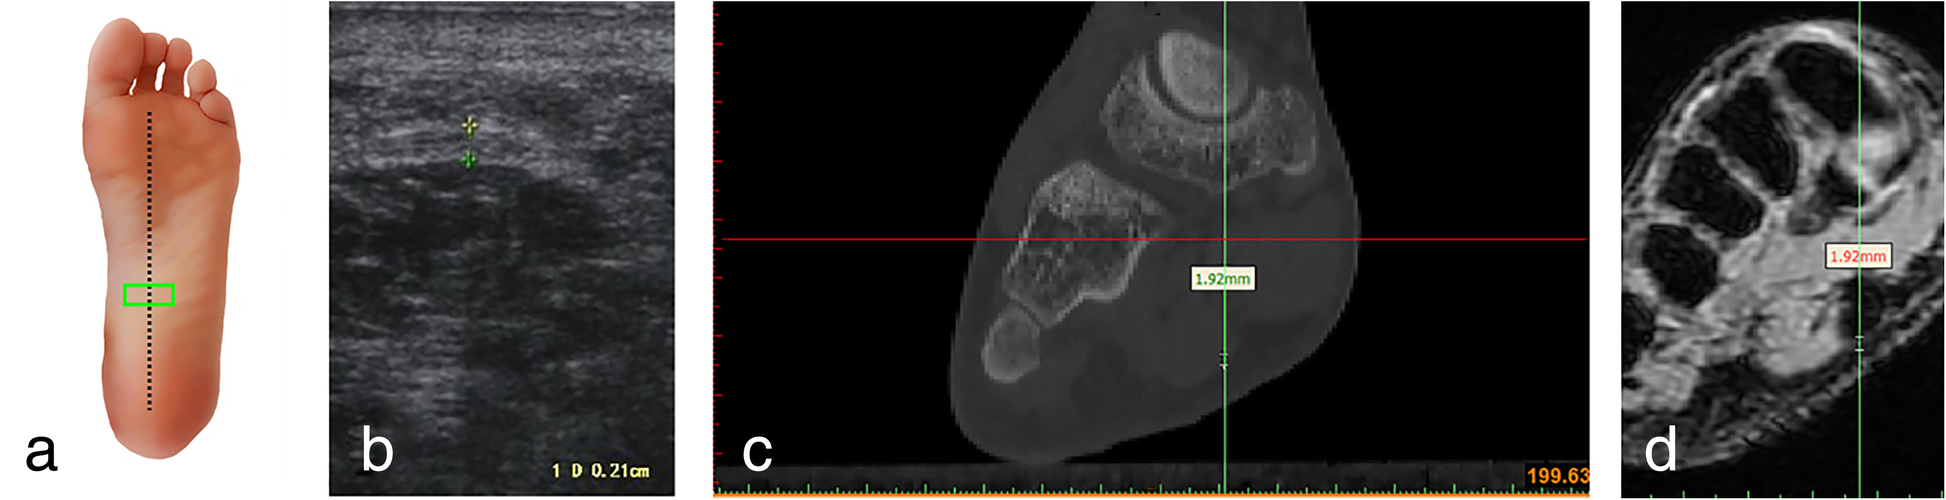

Fig. 4

Ultrasound, CT and MRI measurements of the arch of the plantar fascia (transverse section) a Ultrasonic probe is placed (green panel). b Ultrasonic measurement. c Measuring the thickness of the plantar fascia reconstruction CT images. d Measuring the thickness of the plantar fascia reconstruction MRI images